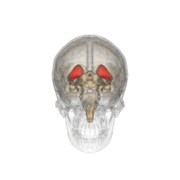

The caudate nuclei are located near the center of the brain, sitting astride the thalamus. There is a caudate nucleus within each hemisphere of the brain. Individually, they resemble a C-shape structure with a wider "head" (caput in Latin) at the front, tapering to a "body" (corpus) and a "tail" (cauda). Sometimes a part of the caudate nucleus is referred to as the "knee" (genu).[5]

The head and body of the caudate nucleus form part of the floor of the anterior horn of the lateral ventricle. After the body travels briefly towards the back of the head, the tail curves back toward the anterior, forming the roof of the inferior horn of the lateral ventricle. This means that a coronal (on a plane parallel to the face) section that cuts through the tail will also cross the body and head of the caudate nucleus.